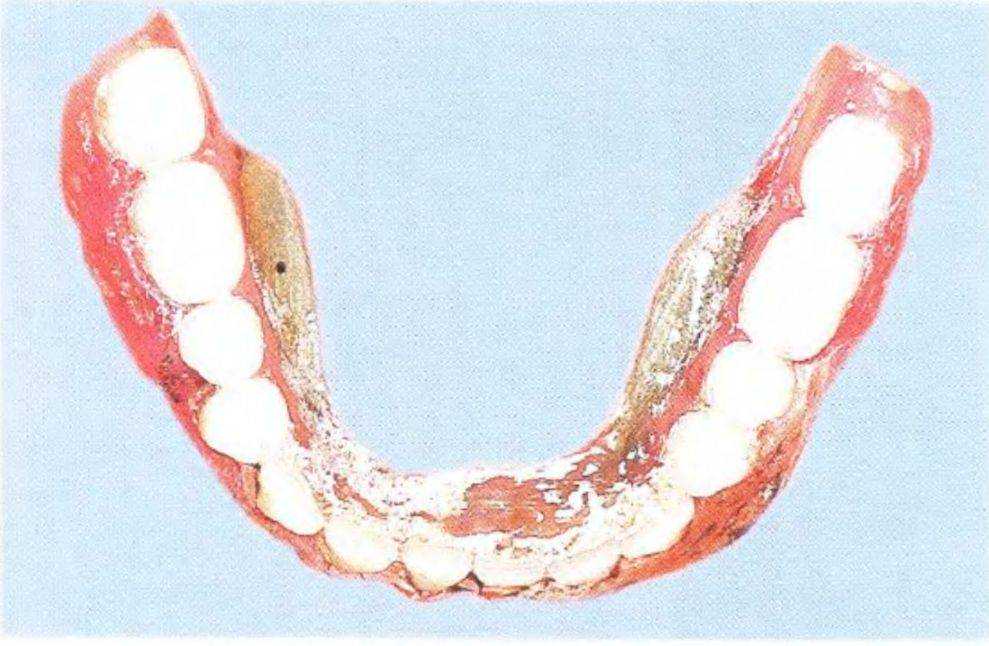

Рис. 3-39d. Съемный частичный протез с литым каркасом.

Съемный частичный протез с литым каркасом. Имеющийся протез не удовлетворял пациентку.